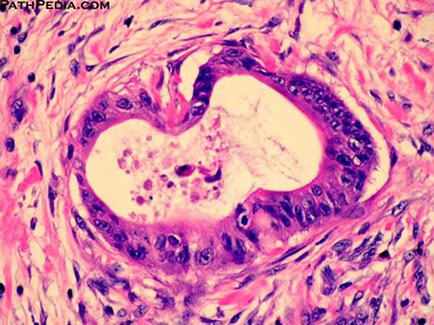

Micro: Benign ducts surrounded by dense lymphoplasmacytic inflam and expansion of periductal space c sclerosis

- storiform fibroblastic prolif [2]

- > 10 IgG4-plasma cells / HPF